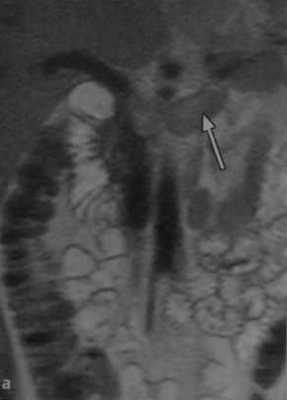

а, b Тромбоз левой почечной вены. Расширение левой почечной вены, которая спереди пересекает аорту (стрелка на рисунке а): (а) Неусиленное фронтальное Т2-взвешенное МР-изображение;

(b) Т1 -взвешенная МР-венография с подавлением сигнала от жировой ткани, полученная в плоскости сравнения после внутривенного введения КВ на основе гадолиния